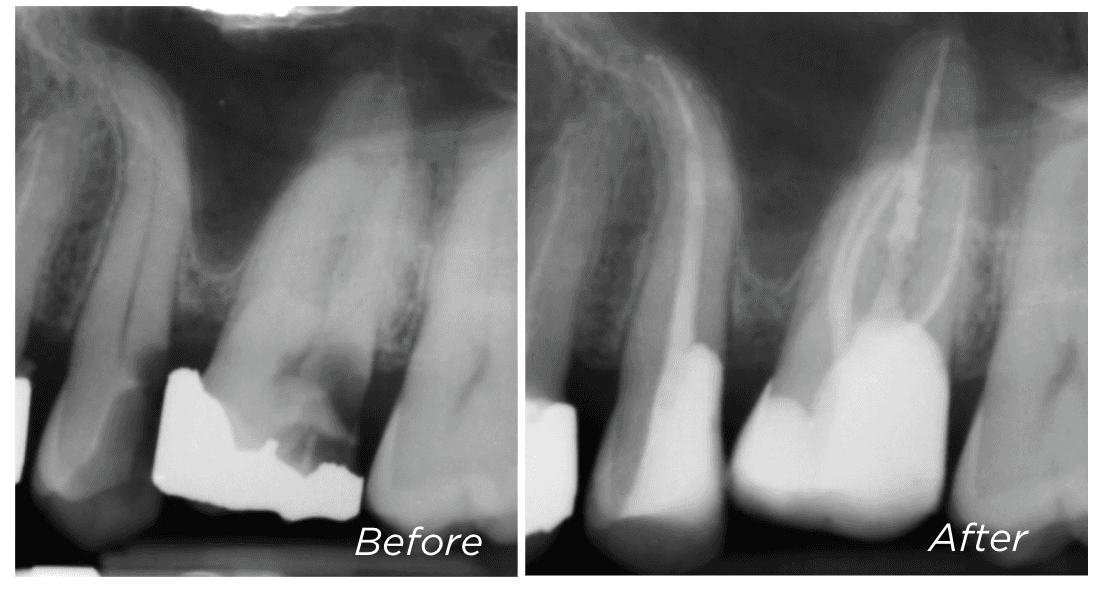

Some teeth are referred to us as “unrestorable” — meaning the decay has extended too deep to reliably place a new filling or crown. But in many cases, we’re able to save these teeth using a technique called deep margin elevation (DME).

This involves carefully removing the old filling and placing a new restoration deeper into the tooth — using special techniques to ensure it is secure and well sealed.

We won’t know if DME is possible until the old filling has been removed and we can assess how much healthy tooth remains. If we’re able to place a well-sealed restoration, the tooth may still be suitable for root canal treatment and long-term restoration.

If DME isn’t an option, surgical crown lengthening may help expose more of the tooth — this is explained in the next section.

Dr Kreena Patel is often referred teeth that others consider unsalvageable — and she will always explore every option to help preserve your natural tooth wherever possible